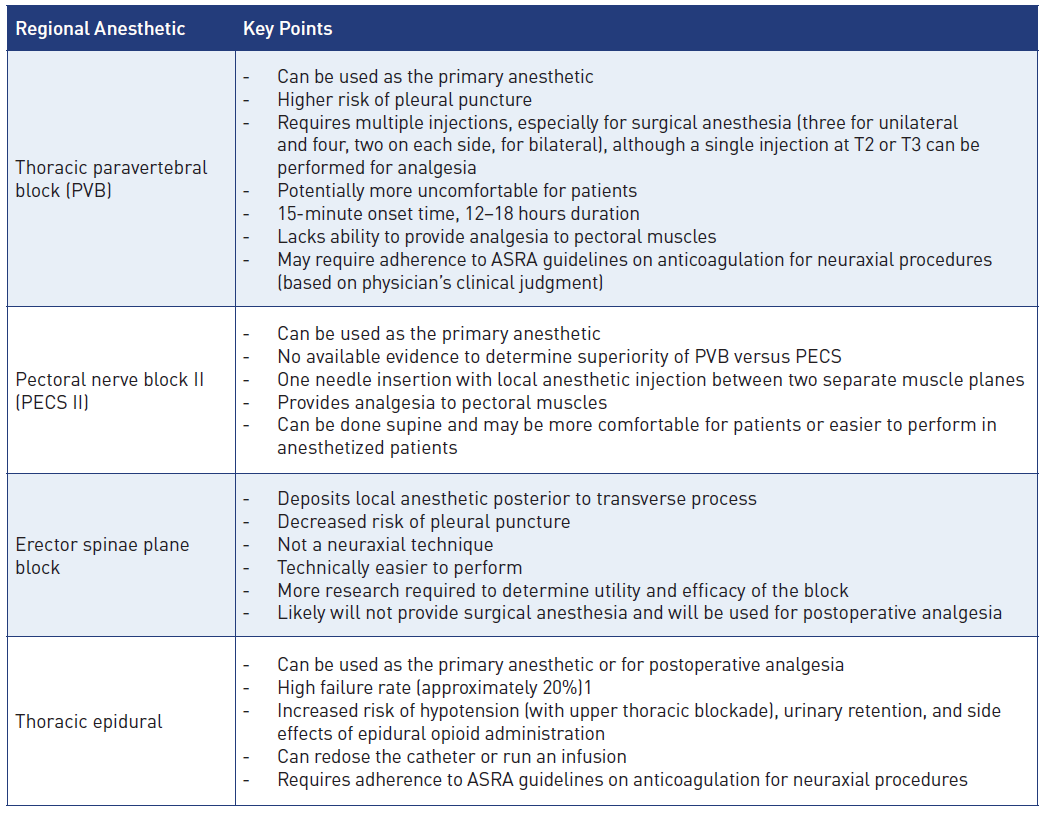

Figure 1: Relevant dermatomes of the breast

Image courtesy of Steven Ethier, DO.

The innervation of the is complex. Branches of the cervical spinal cord and brachial plexus give way to the supraclavicular nerves (C3–C4) as well as the lateral (C5–C7) and medial (C8–T1) pectoral nerves. Those nerves innervate the infraclavicular region and the pectoral muscles, respectively. In the thoracic region, the anterior rami of the spinal nerves give way to the corresponding intercostal nerves supplying their respective dermatome (Figure 1). The intercostobrachial nerve (T2) typically innervates the axilla, whereas T2–T6 innervate the anterior and lateral chest wall.[2]